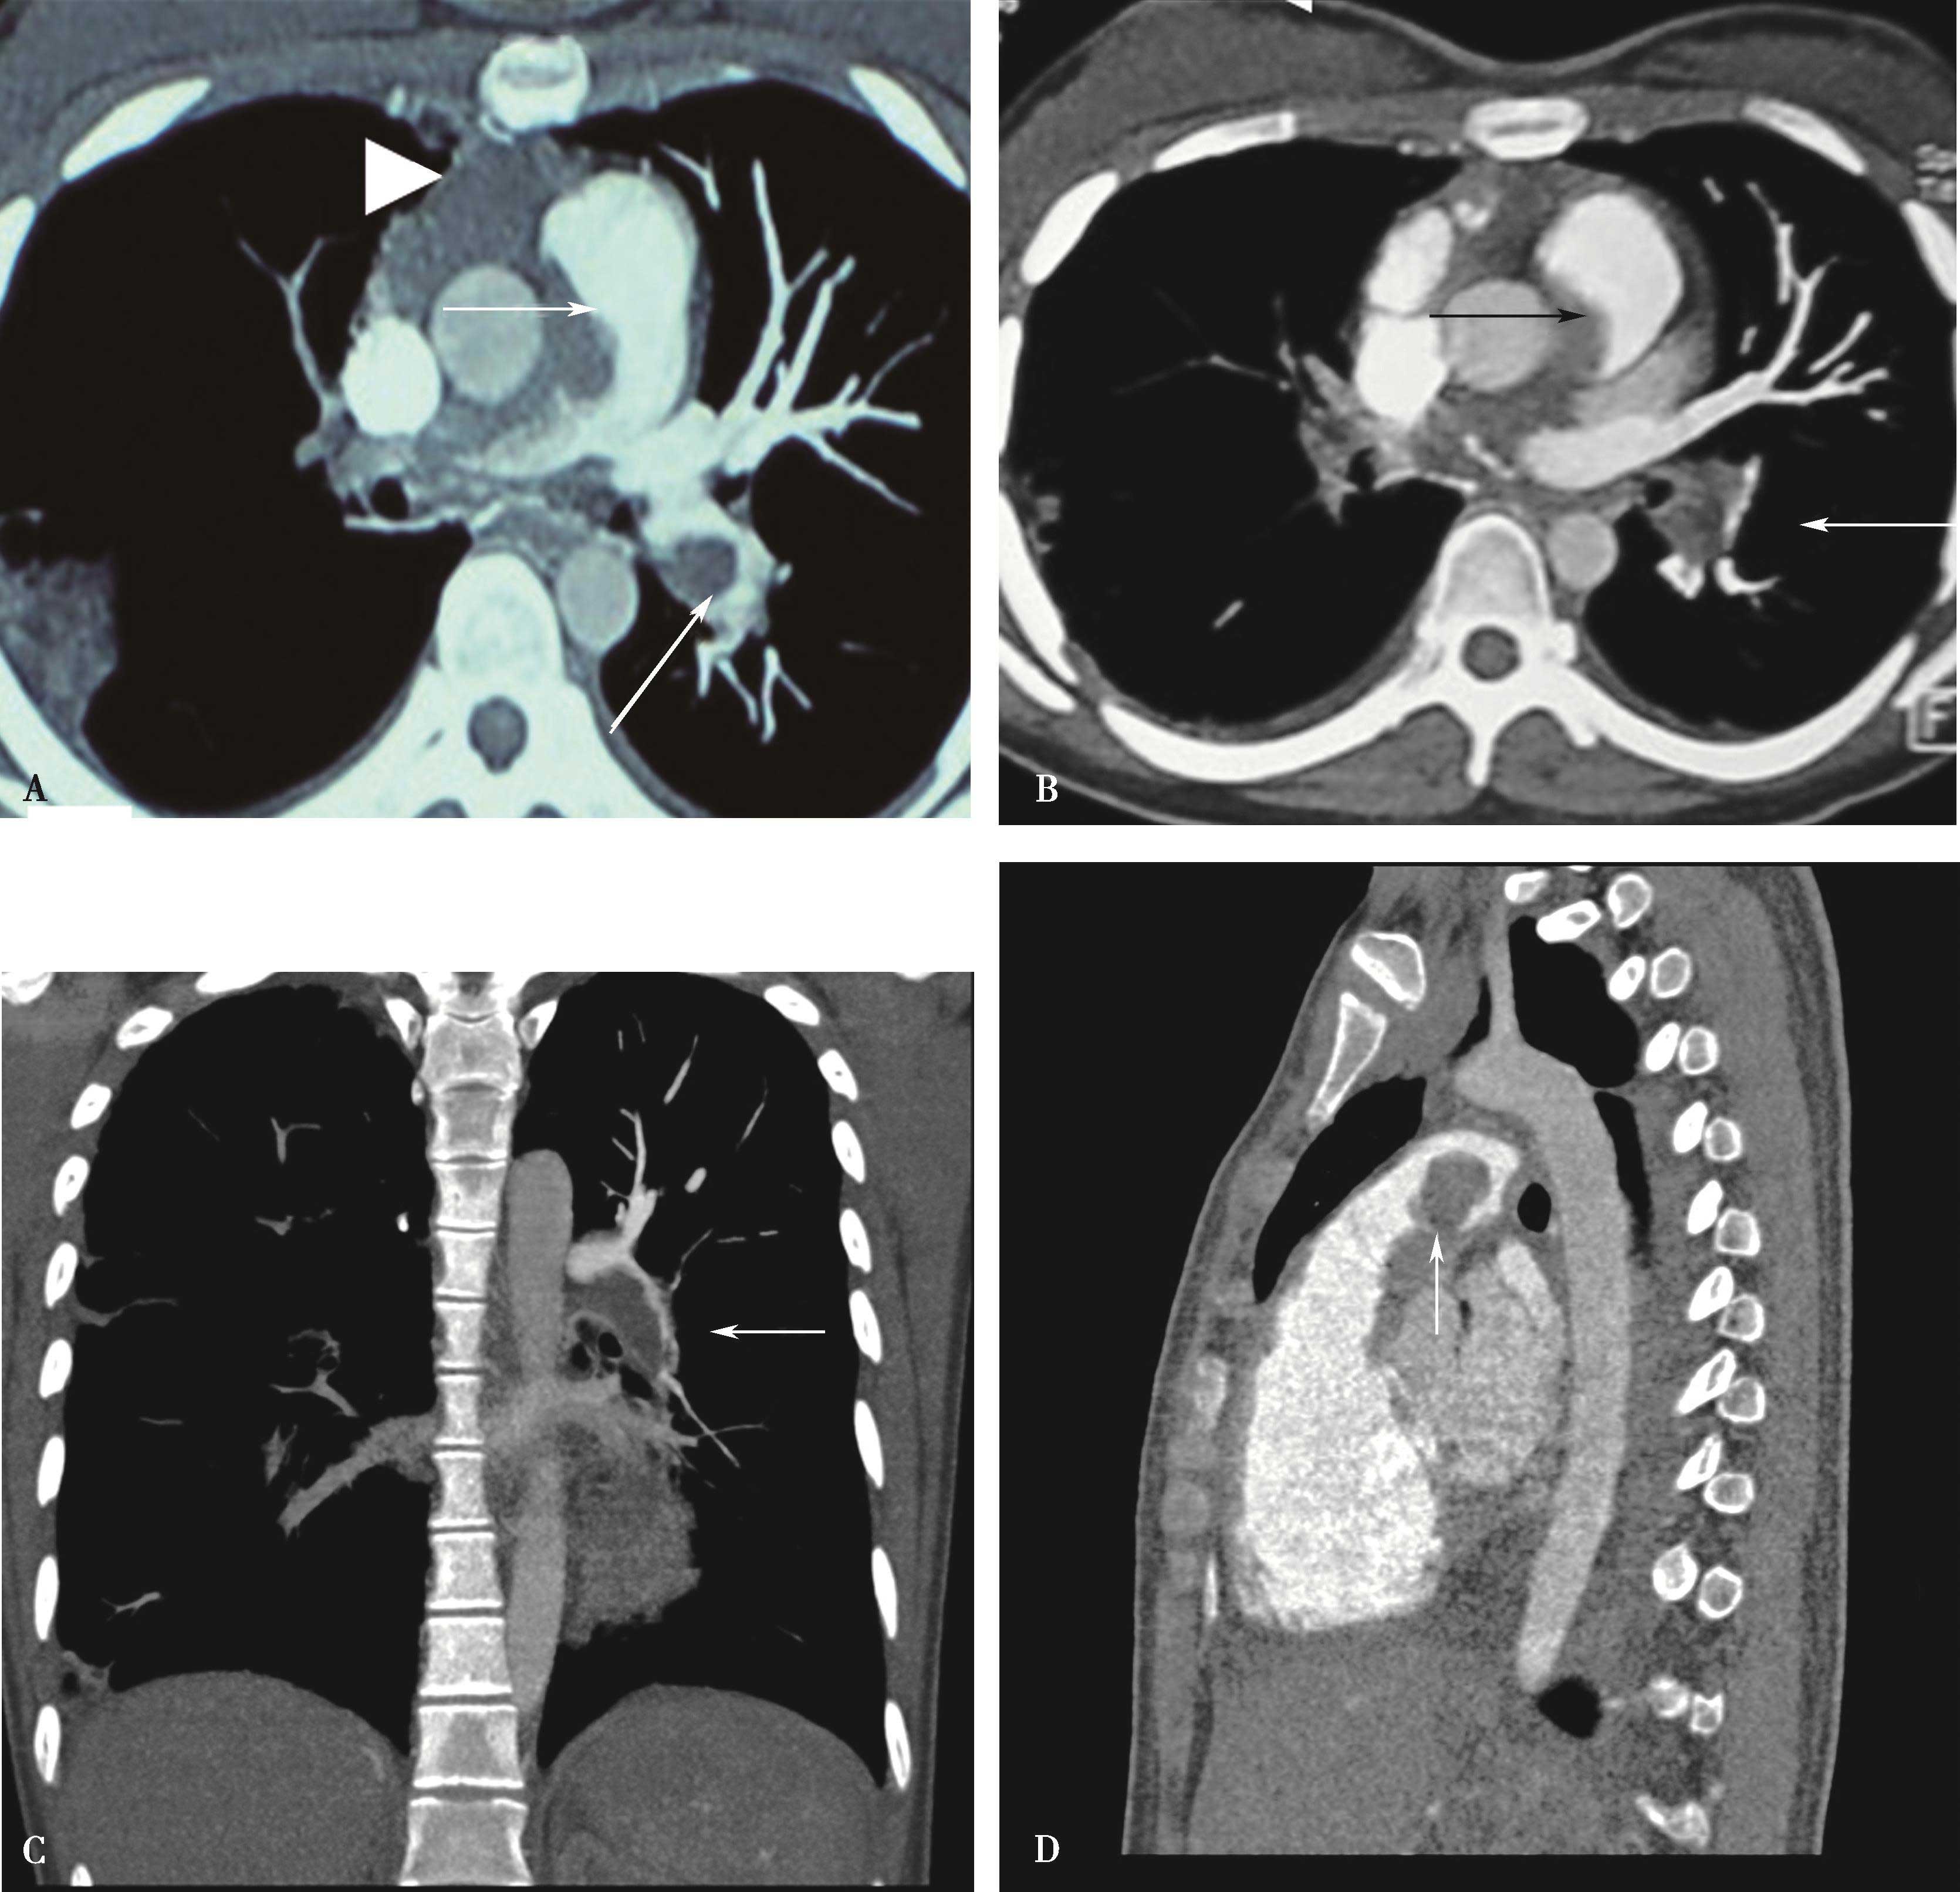

图8-1-4 常规肺动脉CT造影横断图及重建图像

图8-1-5 CTPA两期扫描应用:患者,男,37岁,二尖瓣狭窄,肺循环高压,怀疑肺栓塞。第一期右肺下叶基底段对比剂充盈不充分(ABC↑);第二期充盈充分(DEF↑),排除肺栓塞诊断